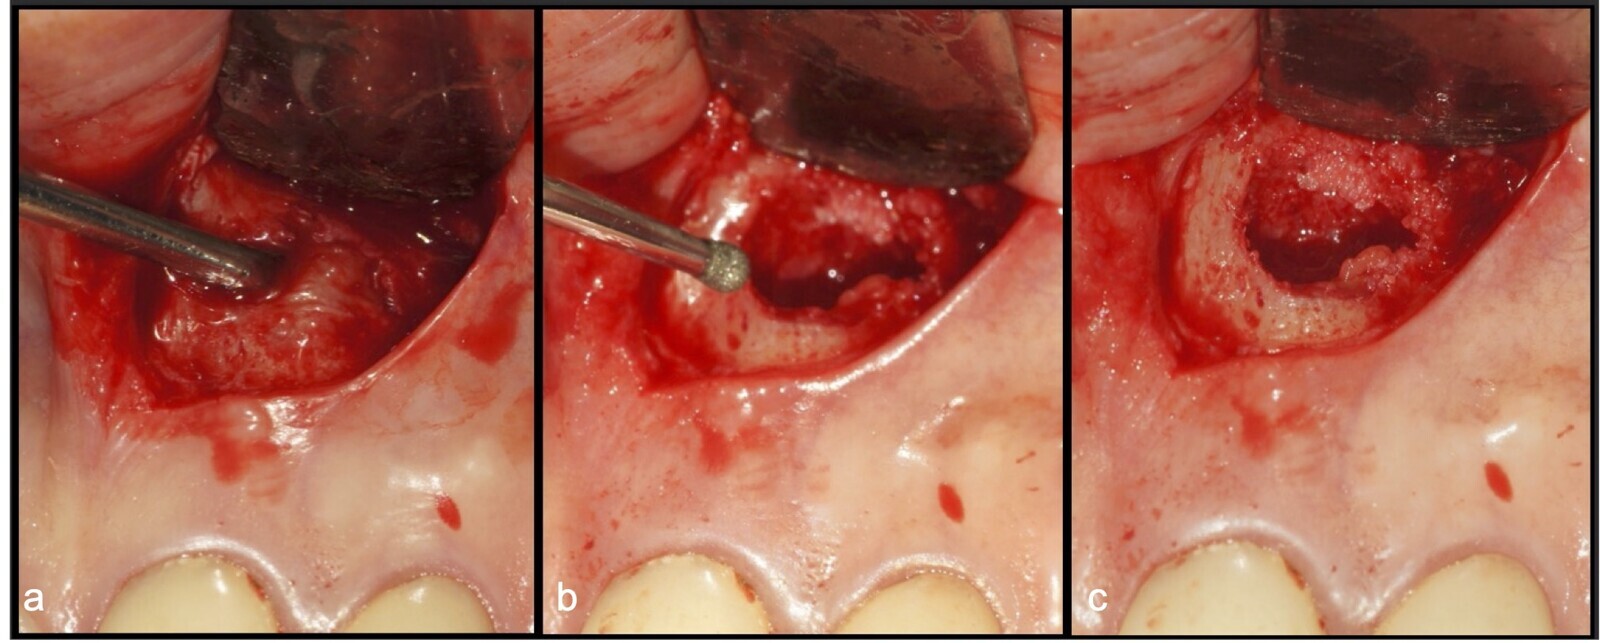

Figura 13. Secuencia de elevación del colgajo semilunar, eliminación de tejido granulomatoso y acceso a la zona periapical de la pieza 2.1 con inserto redondo de punta diamantada (a, b, c).

Figura 14. Acceso con osteotomía selectiva utilizando el inserto redondo de punta diamantada (a). Identificación del ápice y biselado apical con el inserto plano de punta diamantada (b).

Figura 15. Lecho quirúrgico limpio y delimitado (a, b, c).